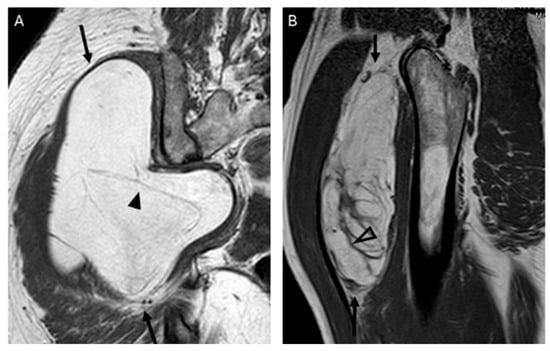

In total, 97–100% of tumors with homogeneous fat signal in the three sequences (p value < 0.001) were lipomas, and 55–61% of lesions with heterogeneous signal were lipomas (Figure 1).

Figure 1.

Coronal T1 weighted (T1W) images: (A) homogeneous lipomatous (completely fatty) tumor in the left arm (arrow), and (B) heterogeneous lipomatous mass in the left thigh, with one non-fat nodule (*) and multiple septa. The diagnosis for both tumors is lipoma, confirmed as MDM2 negative.

In our series, the lipomas showed both homogeneous and heterogenous fat signal intensity, while all ALTs were heterogenous tumors. Based on this criterion—the signal intensity of the tumor on MRI—some lipomas may be misinterpreted as ALT, but the opposite is not true; no ALTs would be misdiagnosed as a lipoma. With homogeneous hyperintensity on SE T1 and TSE T2 sequences, and complete suppression of the fat signal using fat suppression techniques, the diagnosis of lipoma can be made with high confidence. In contrast, heterogeneous tumors may be either a lipoma or an ALT (Figure 4) Therefore, homogeneous signal rules out ALT, while heterogeneous signal does not rule out lipoma (Figure 1).